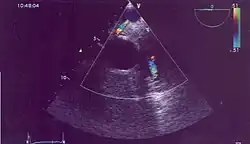

En échographie, on met parfois en évidence une fistule entre la coronaire gauche et la coronaire droite dilatée et absence de visualisation de la coronaire gauche qui ne naît pas de l'ostium coronaire mais qui sort de la partie antérieure du tronc coronaire et flux continu diastolique dans l'artère pulmonaire vélocité basse éliminant un canal artériel. Elle se situe parfois dans une branche de l'artère pulmonaire mais dans ce cas nécessite le scanner.